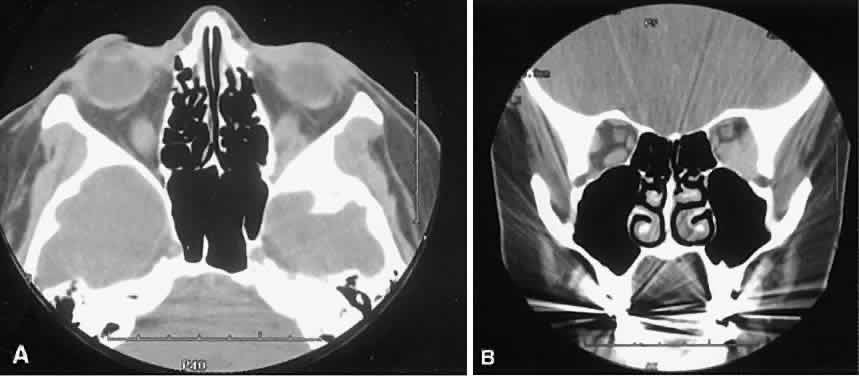

An appreciation for the various pathologic processes that affect the orbit is facilitated by an understanding of the normal orbital anatomy (Fig. 1). The orbit is a pyramid-shaped bony structure bounded inferiorly by the maxillary sinus, medially by the ethmoidal sinus, and superiorly by the frontal sinus. The sphenoidal sinus is situated posteriorly along the medial orbital wall and has a common wall with the optic canal. The lacrimal gland lies within its fossa located in the superior temporal aspect of the orbit and can be seen on both axial and coronal views.

Fig. 1. Normal anatomy. A. Axial scan through the plane of the optic nerve. Note the normal size of the horizontal rectus muscles and the undulating course of the optic nerve. B. Coronal view of the right orbit. The plane of section is slightly oblique to avoid dental artifacts and is immediately behind the right globe, which is partially volume averaged inferiorly. The arrow points to the optic nerve.

The extraocular muscles (EOMs), with the exception of the inferior oblique, originate from the anulus of Zinn in the orbital apex. The inferior oblique takes its origin from the frontal process of the maxilla and is seen occasionally on CT imaging. The superior oblique, after originating from the anulus, courses along the superior nasal orbital wall just above the medial rectus muscle before passing through the trochlea. The rectus muscles conveniently form a muscle cone, which is sometimes helpful in terms of differential diagnosis. Before thinner axial slices and multiplanar imaging were available, an enlarged inferior rectus muscle often was imaged as an apical mass, especially if dysthy-roid optic neuropathy was present. The importance of imaging from two different planes cannot be overemphasized in this situation.